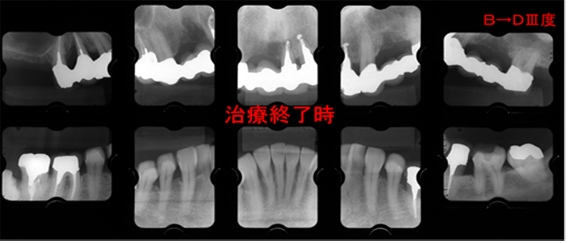

(第四症例)

他院からの歯周治療依頼にて来院。 6は初診時近遠心に10mm以上のプロービング値とⅢ度根分岐部病変を認めました。このケースは根分岐部に対する器具のアクセスのしやすさ、術後のメインテナンスのしやすさを考え歯髄処置を行い、根分岐部の水平的な深さをできるだけ浅くしたうえで再生療法を行いました。

本来は3種併用の適応ケースでしたが、歯肉が薄く、また遠方からの来院ということでこまめな

術後の対応もできないことから、エムドゲイン+移植骨による2種併用の再生療法で対応しました。しかしながら治療終了時には近遠心とも3mmと大きく改善し骨の再生を認めます。